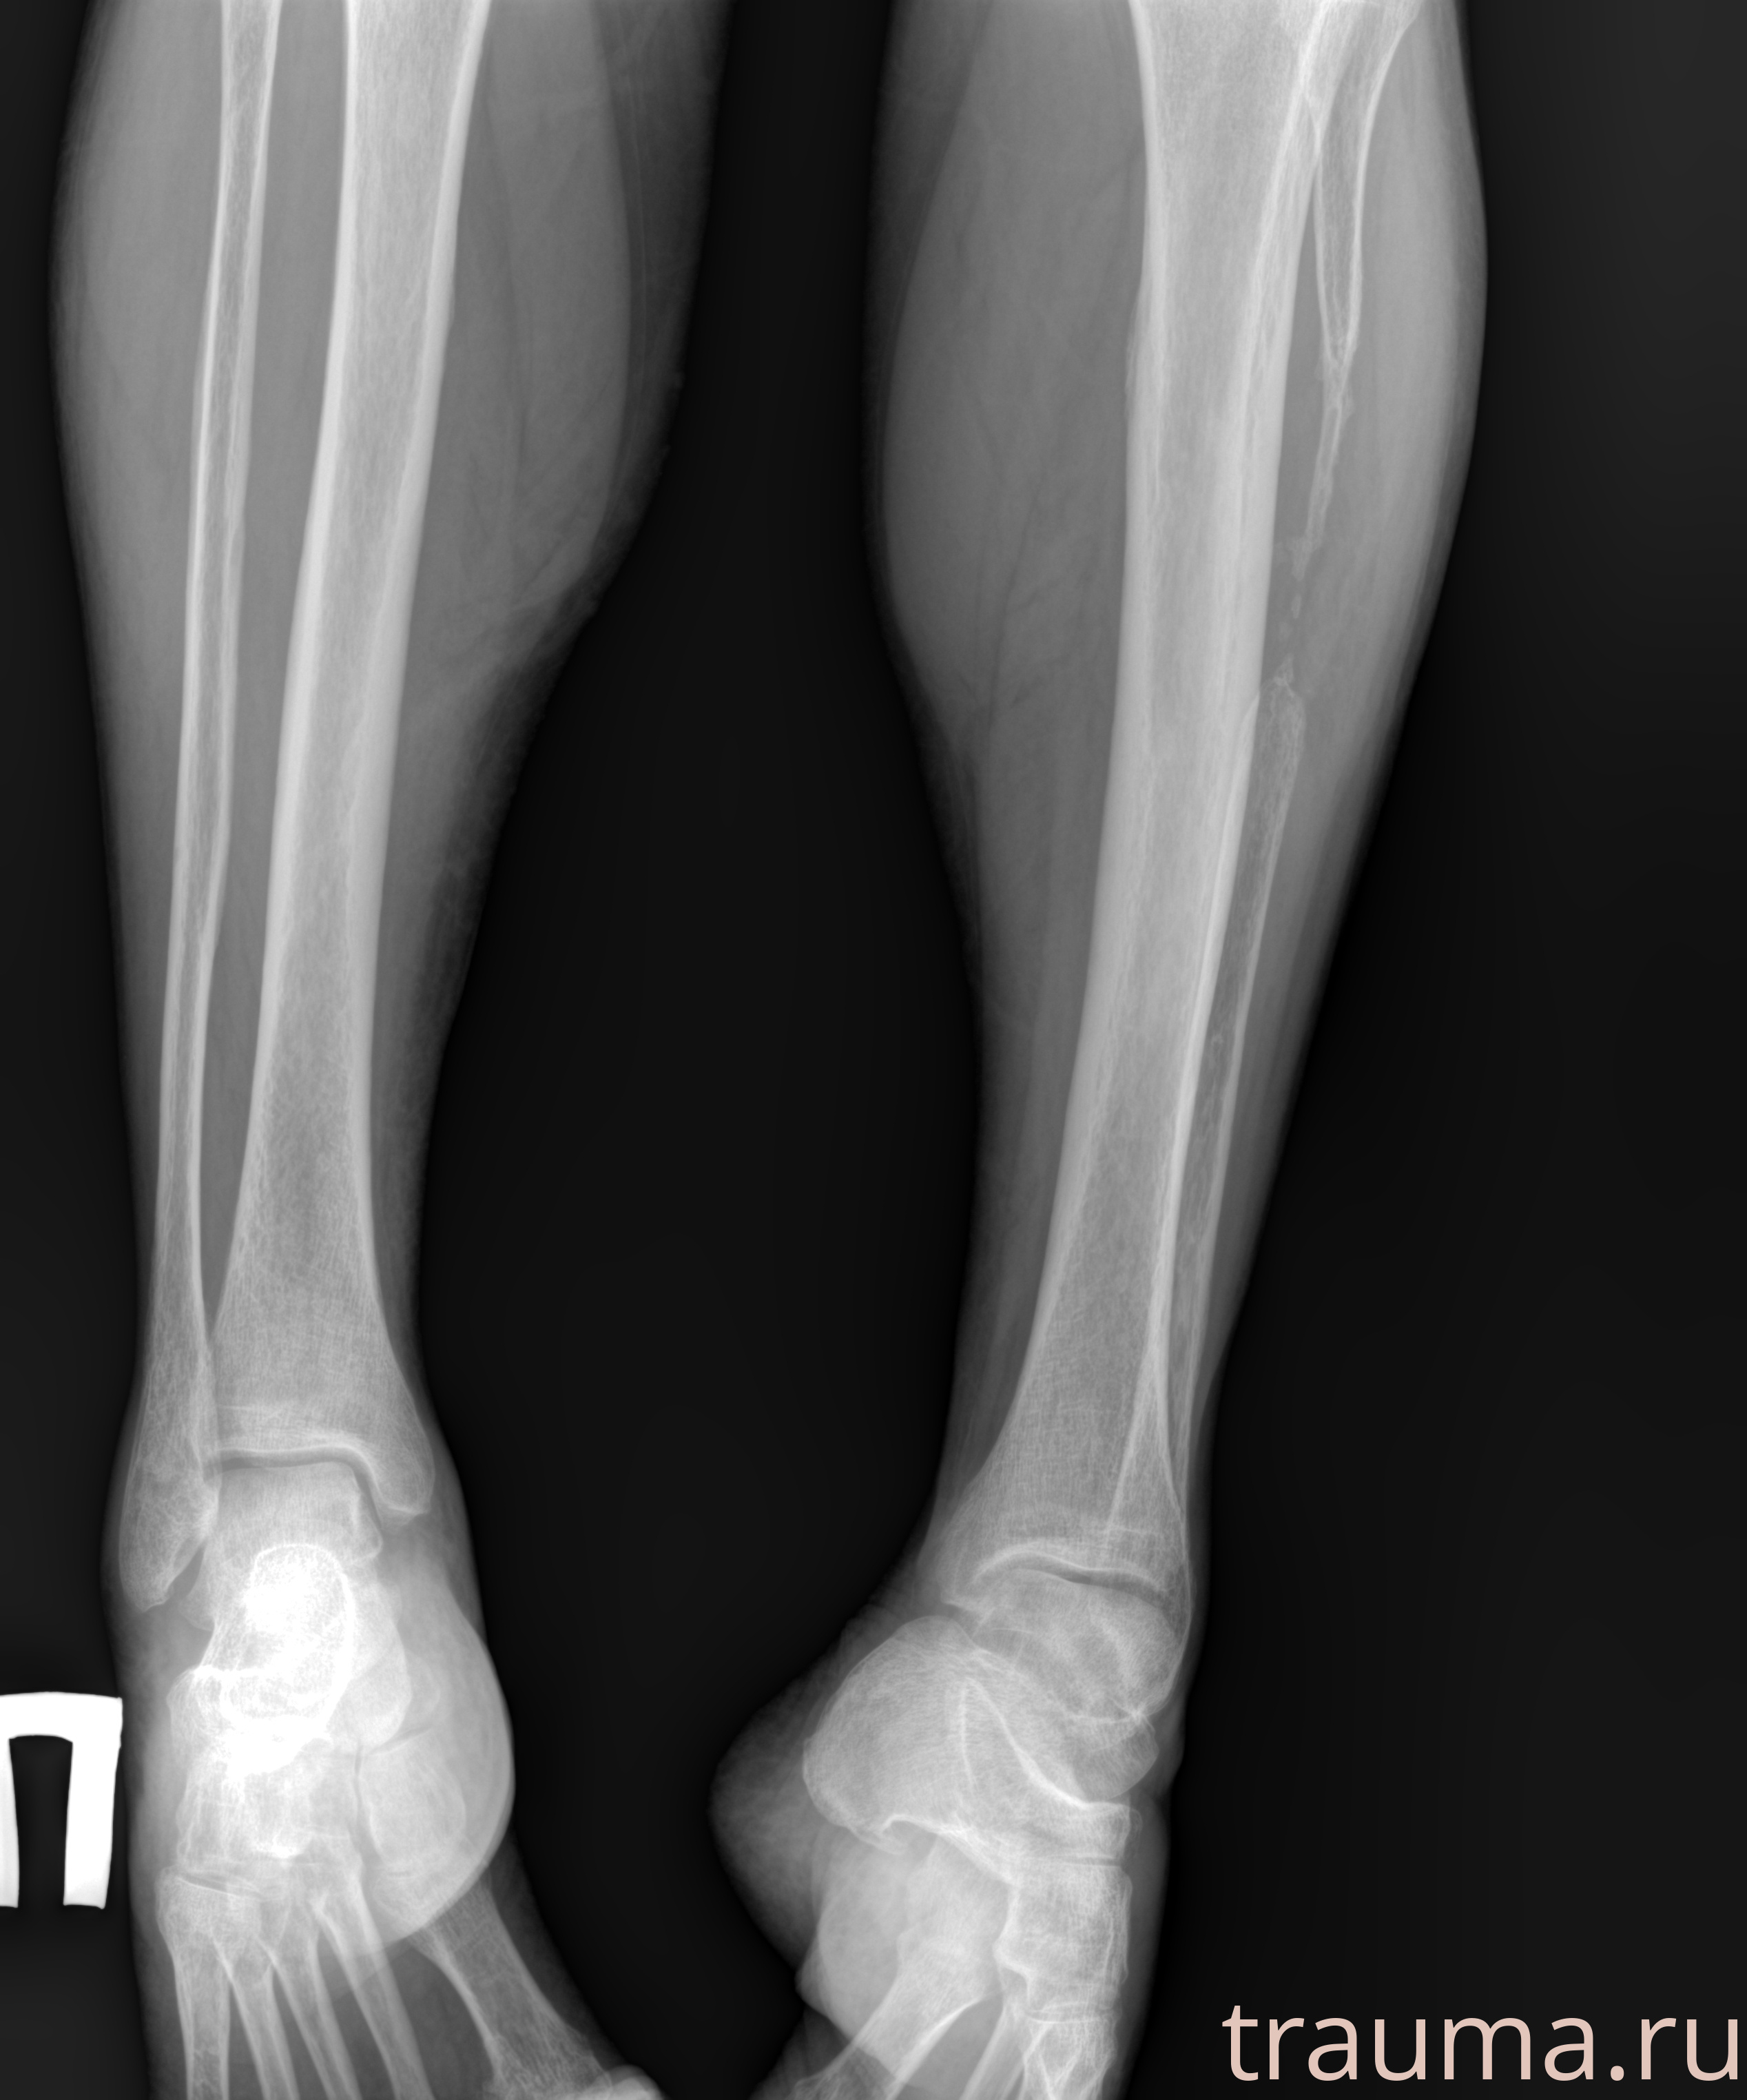

Рентген на дому: по вашему адресу приезжает врач-рентгенолог, травматолог-ортопед с мобильным рентгеновским аппаратом, проводит диагностику травмы или заболевания, делает необходимые рентгенограммы, дает рекомендации по дальнейшему лечению. Получить качественные снимки в домашних условиях возможно благодаря уникальной методике, разработанной МосРентген Центром для института  Склифосовского